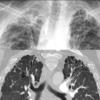

IPF axial

Date: 04/02/2014

Views: 3842